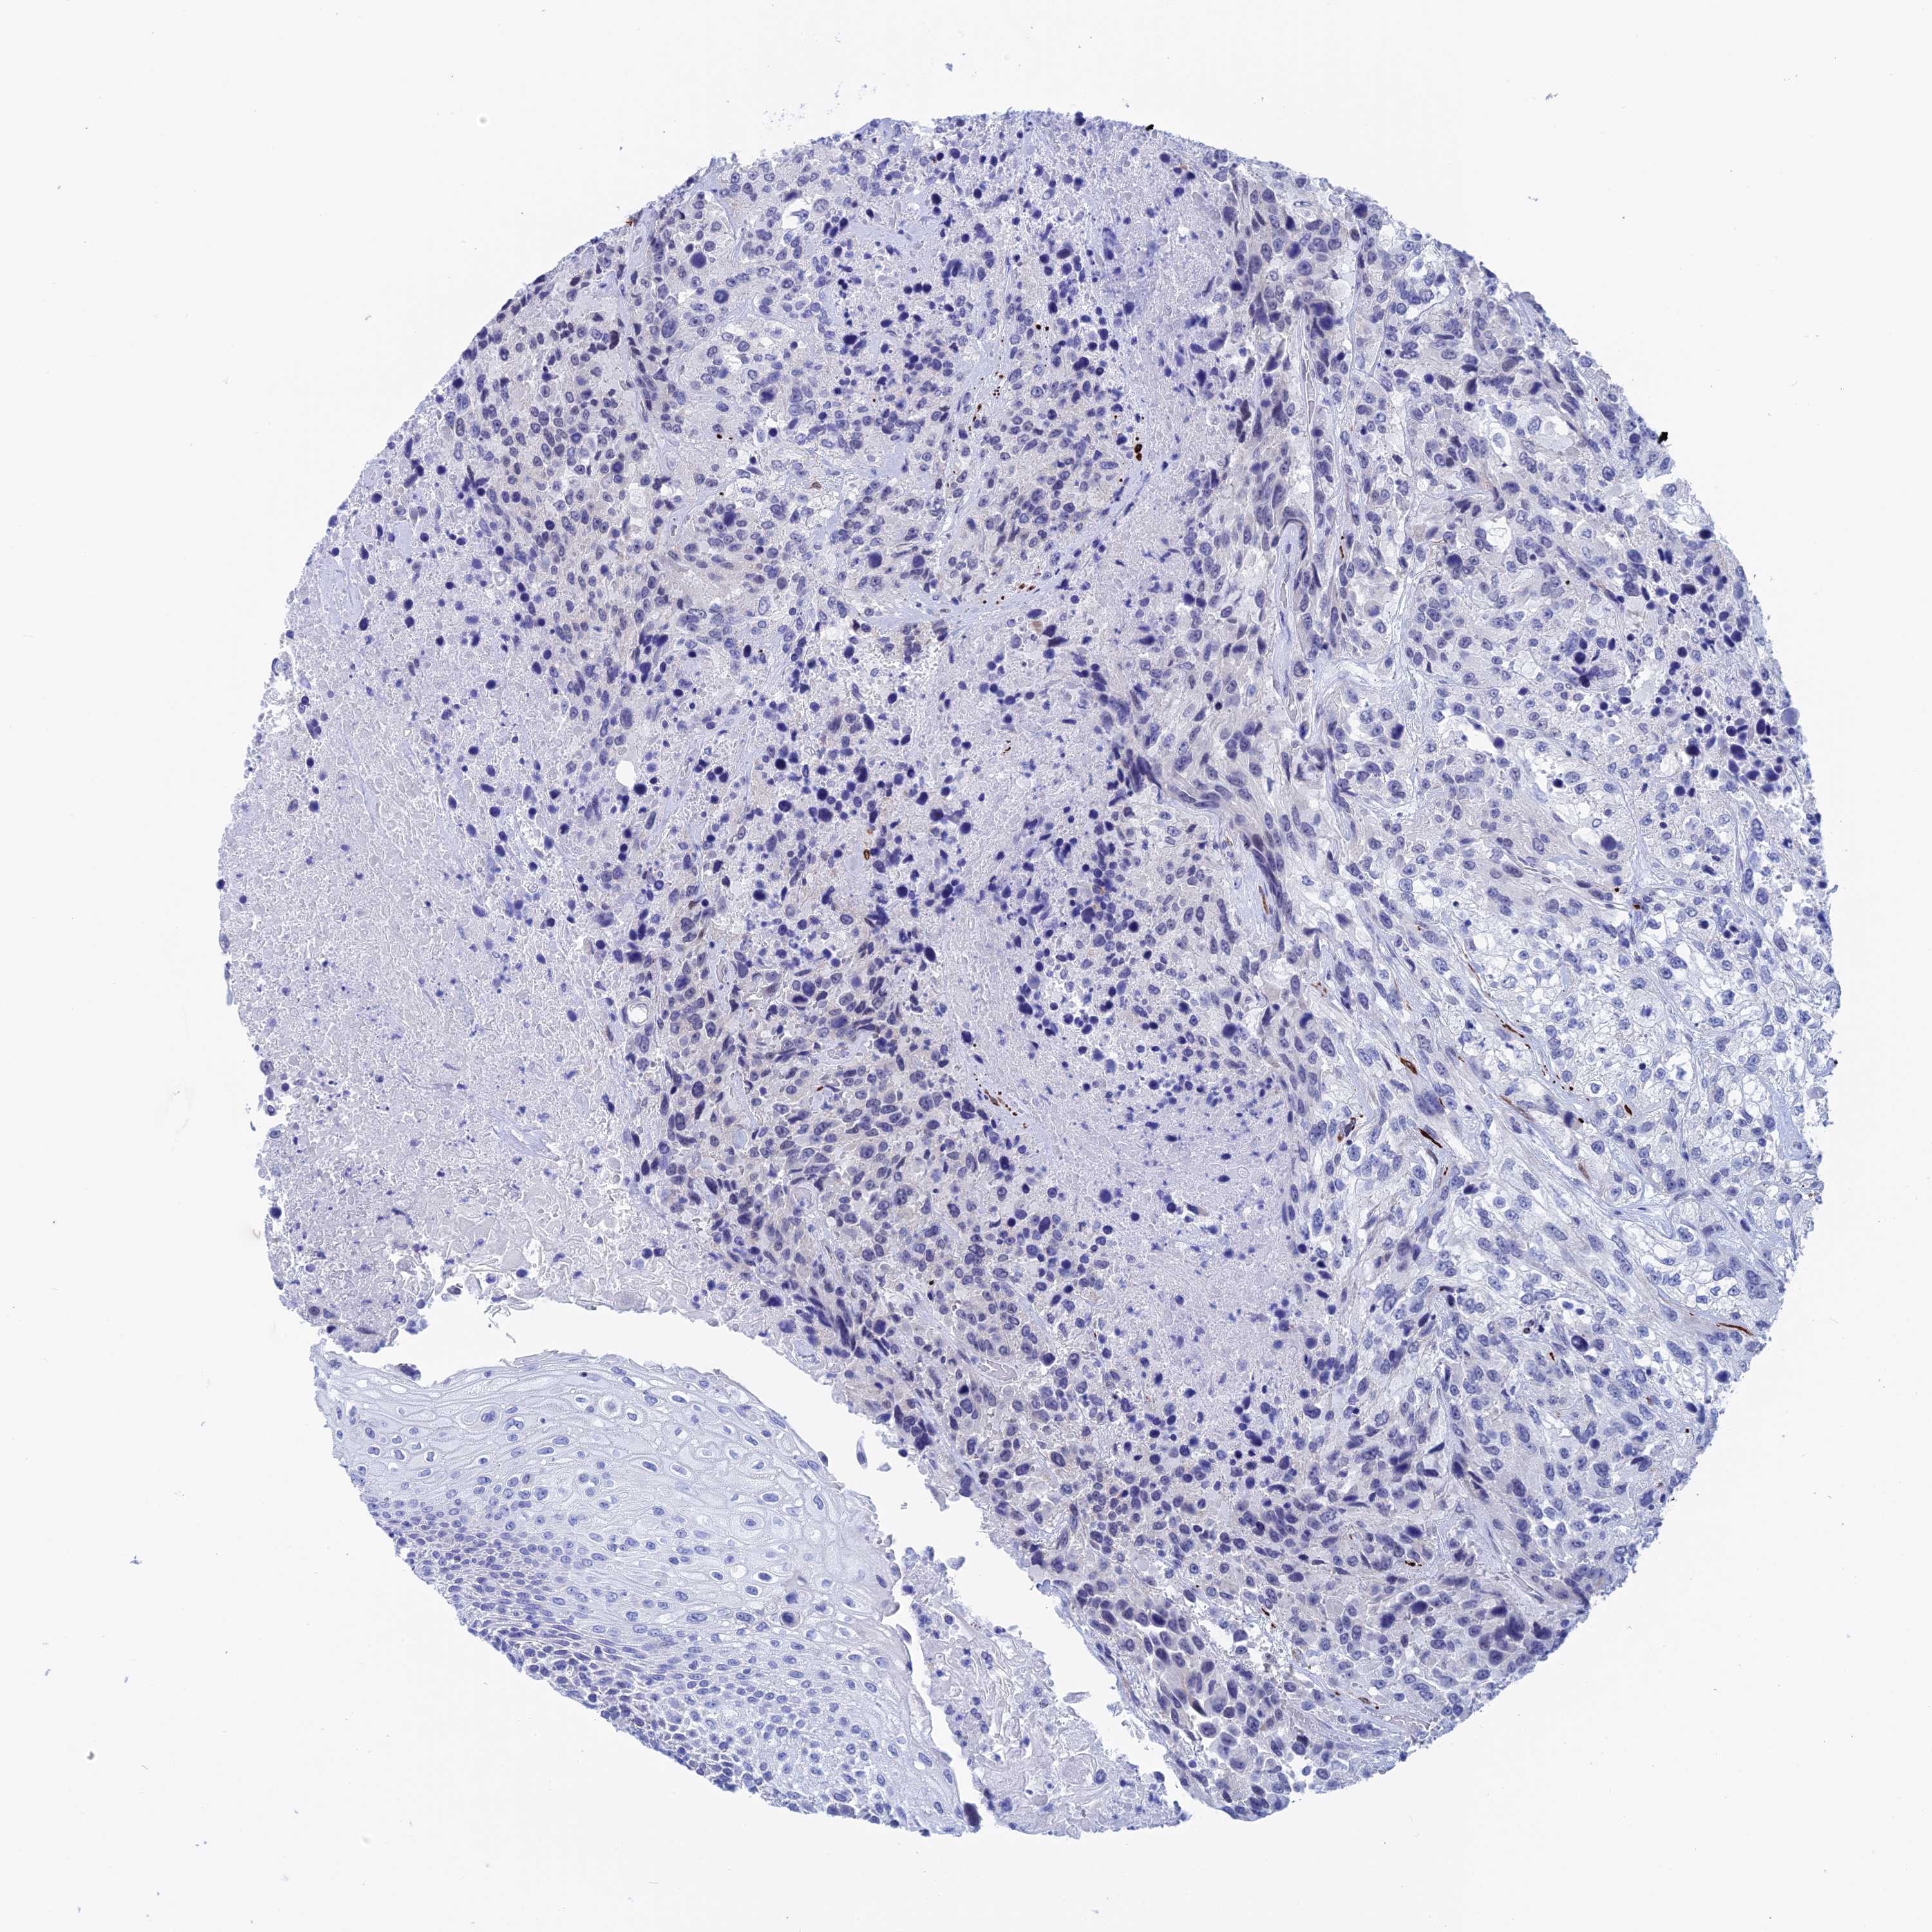

UROTHELIAL CANCER - Protein expressioni

A mouse-over function shows sample information and annotation data. Click on an image to view it in a full screen mode. Samples can be filtered based on level of antibody staining by selecting one or several of the following categories: high, medium, low and not detected. The assay and annotation is described here.

Antibody stainingi

Antibody staining in the annotated cell types in the current human tissue is reported as not detected, low, medium, or high, based on conventional immunohistochemistry profiling in selected tissues. This score is based on the combination of the staining intensity and fraction of stained cells.

Each image is clickable and will lead to virtual microscopy that enables deeper exploration of all samples and also displays staining intensity scores, fraction scores and subcellular localization as well as patient and tissue information for each sample.

Antibody HPA042629

Antibody HPA042838

Staining

High

Medium

Low

Not detected

Intensity

Strong

Moderate

Weak

Negative

Quantity

>75%

75%-25%

<25%

None

Location

Nuclear

Cytoplasmic/membranous

Cytoplasmic/membranous,nuclear

Urothelial carcinoma, High grade

Urothelial carcinoma, Low grade